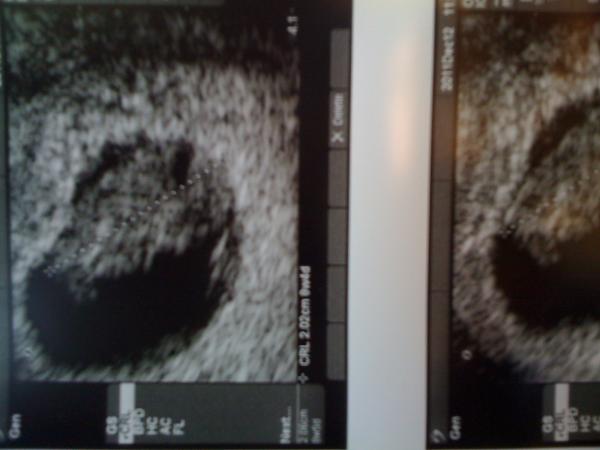

Perhaps I'll follow this up with an SBR shoutout video when she goes into labor.